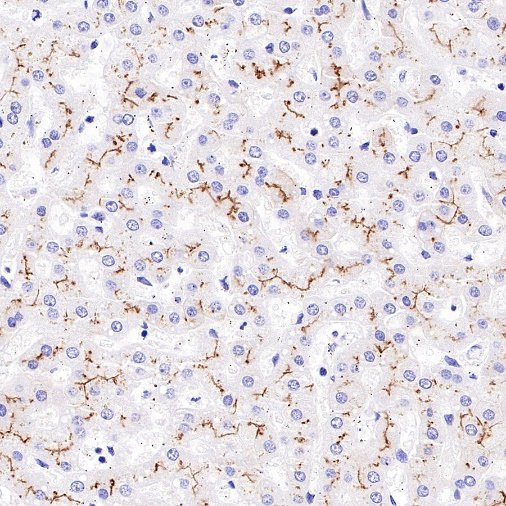

Immunohistochemistry

IHC shows positive staining in paraffin-embedded human kidney. Anti-MDR1/ABCB1 antibody was used at 1/1000 dilution, followed by a HRP Polymer for Mouse & Rabbit IgG (ready to use). Counterstained with hematoxylin. Heat mediated antigen retrieval with Tris/EDTA buffer pH9.0 was performed before commencing with IHC staining protocol.